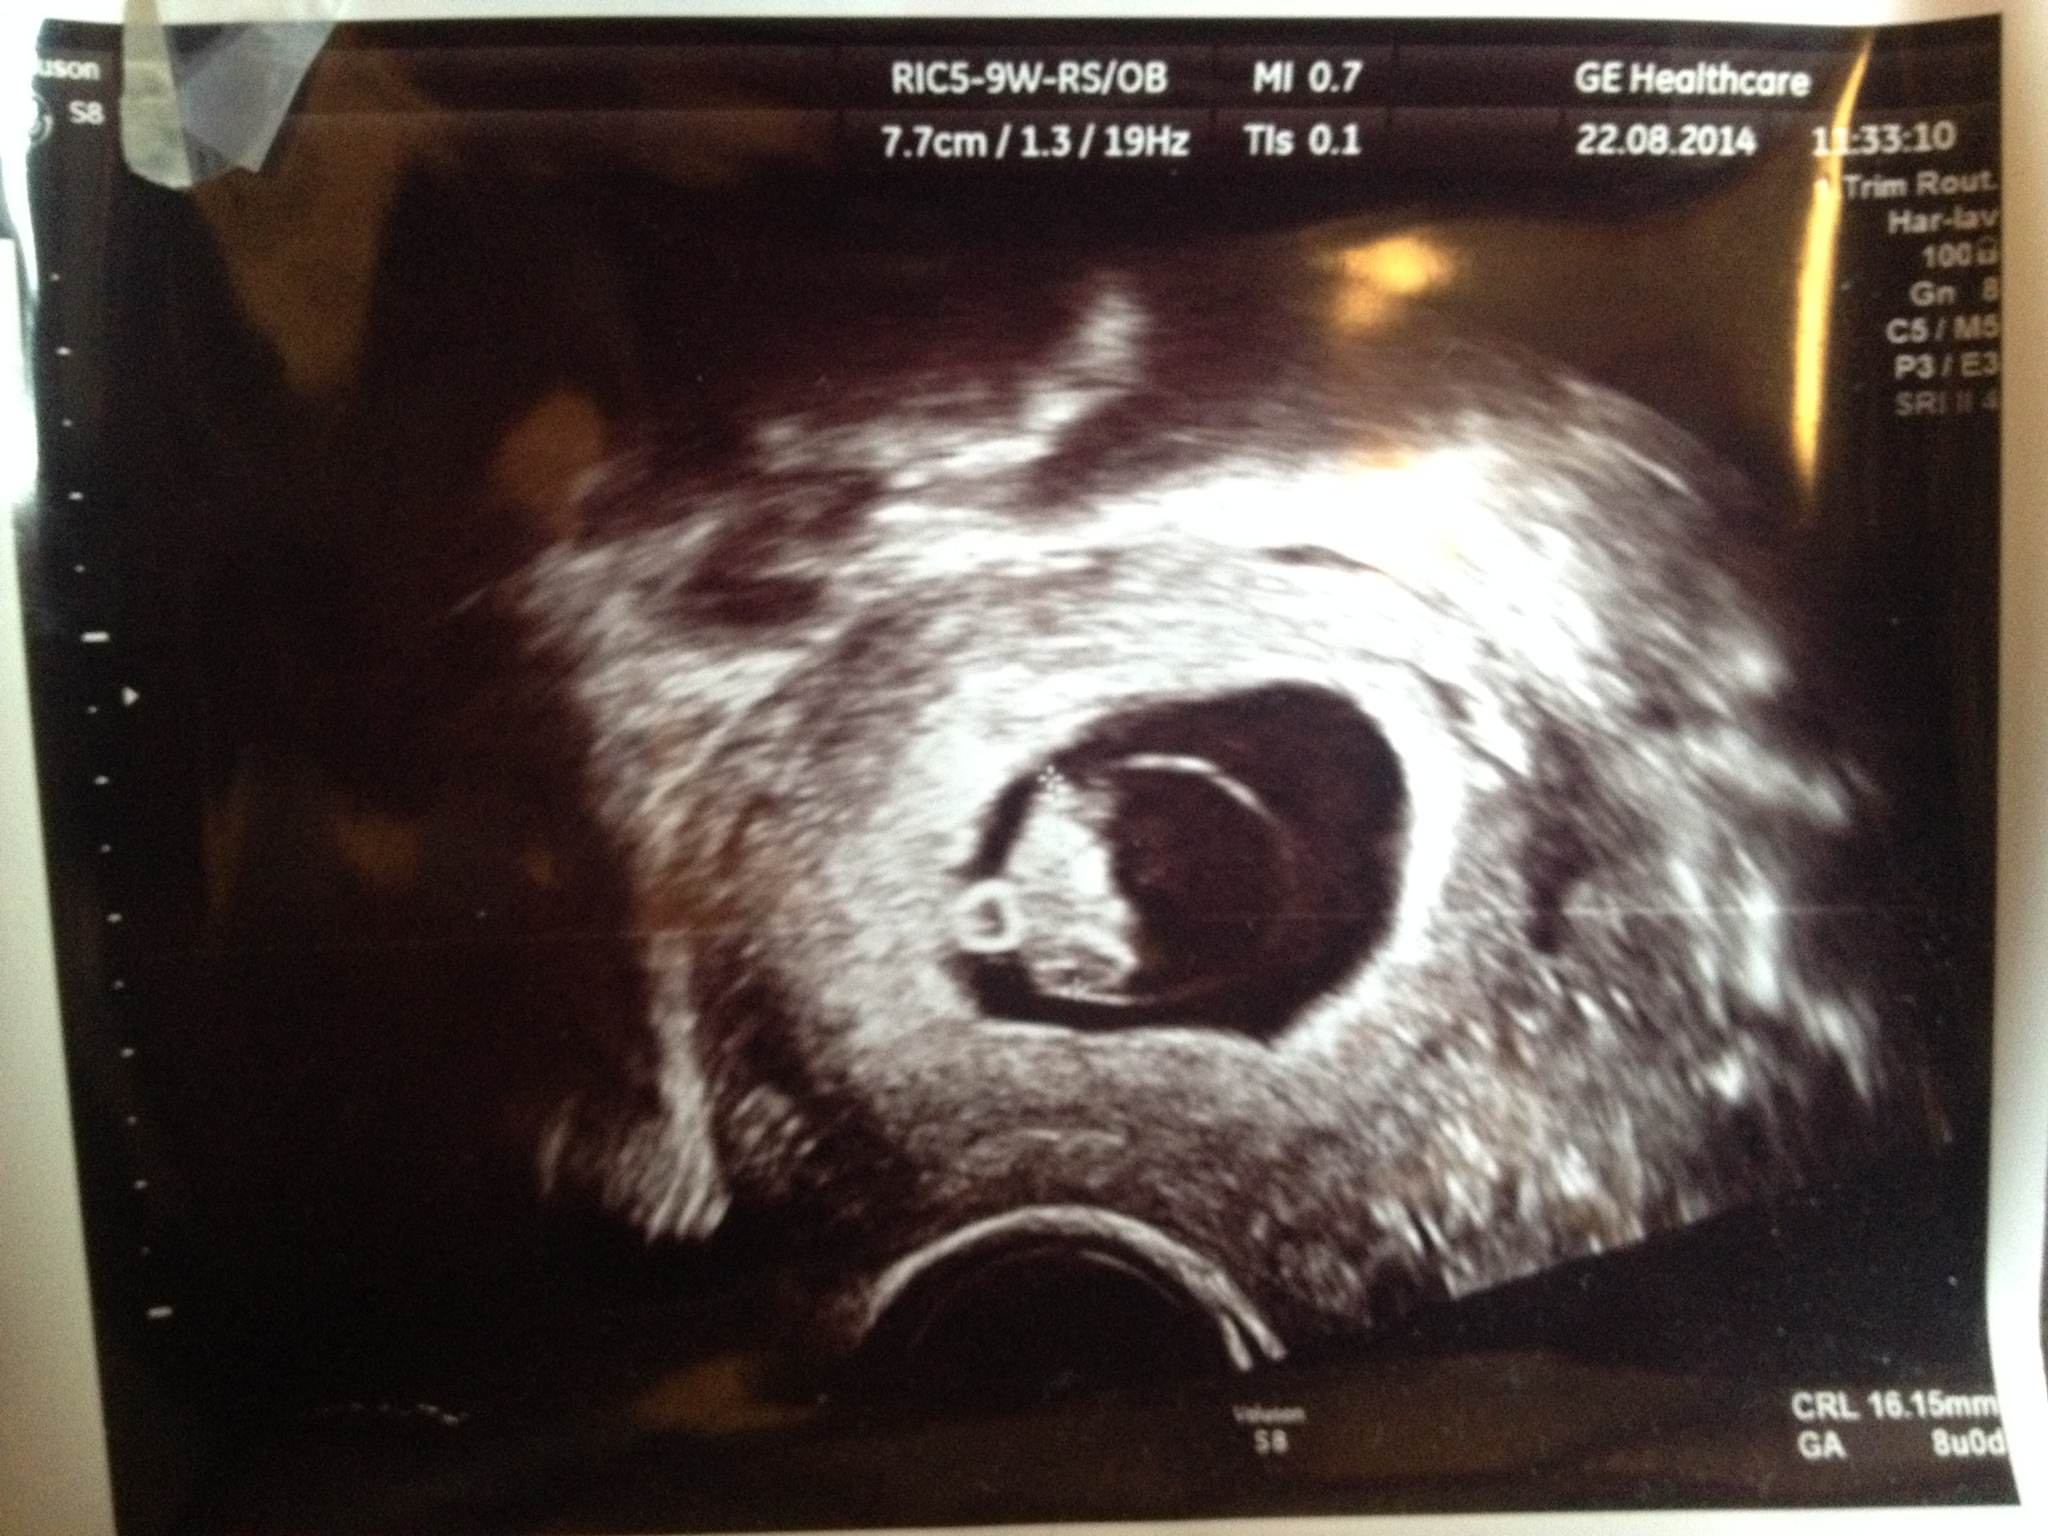

Would love to hear any guesses. Thanks :baby:Attachment 21668

Was this transvaginal? If so 8 say definitely boy

Yes it was....so that means it's flipped?